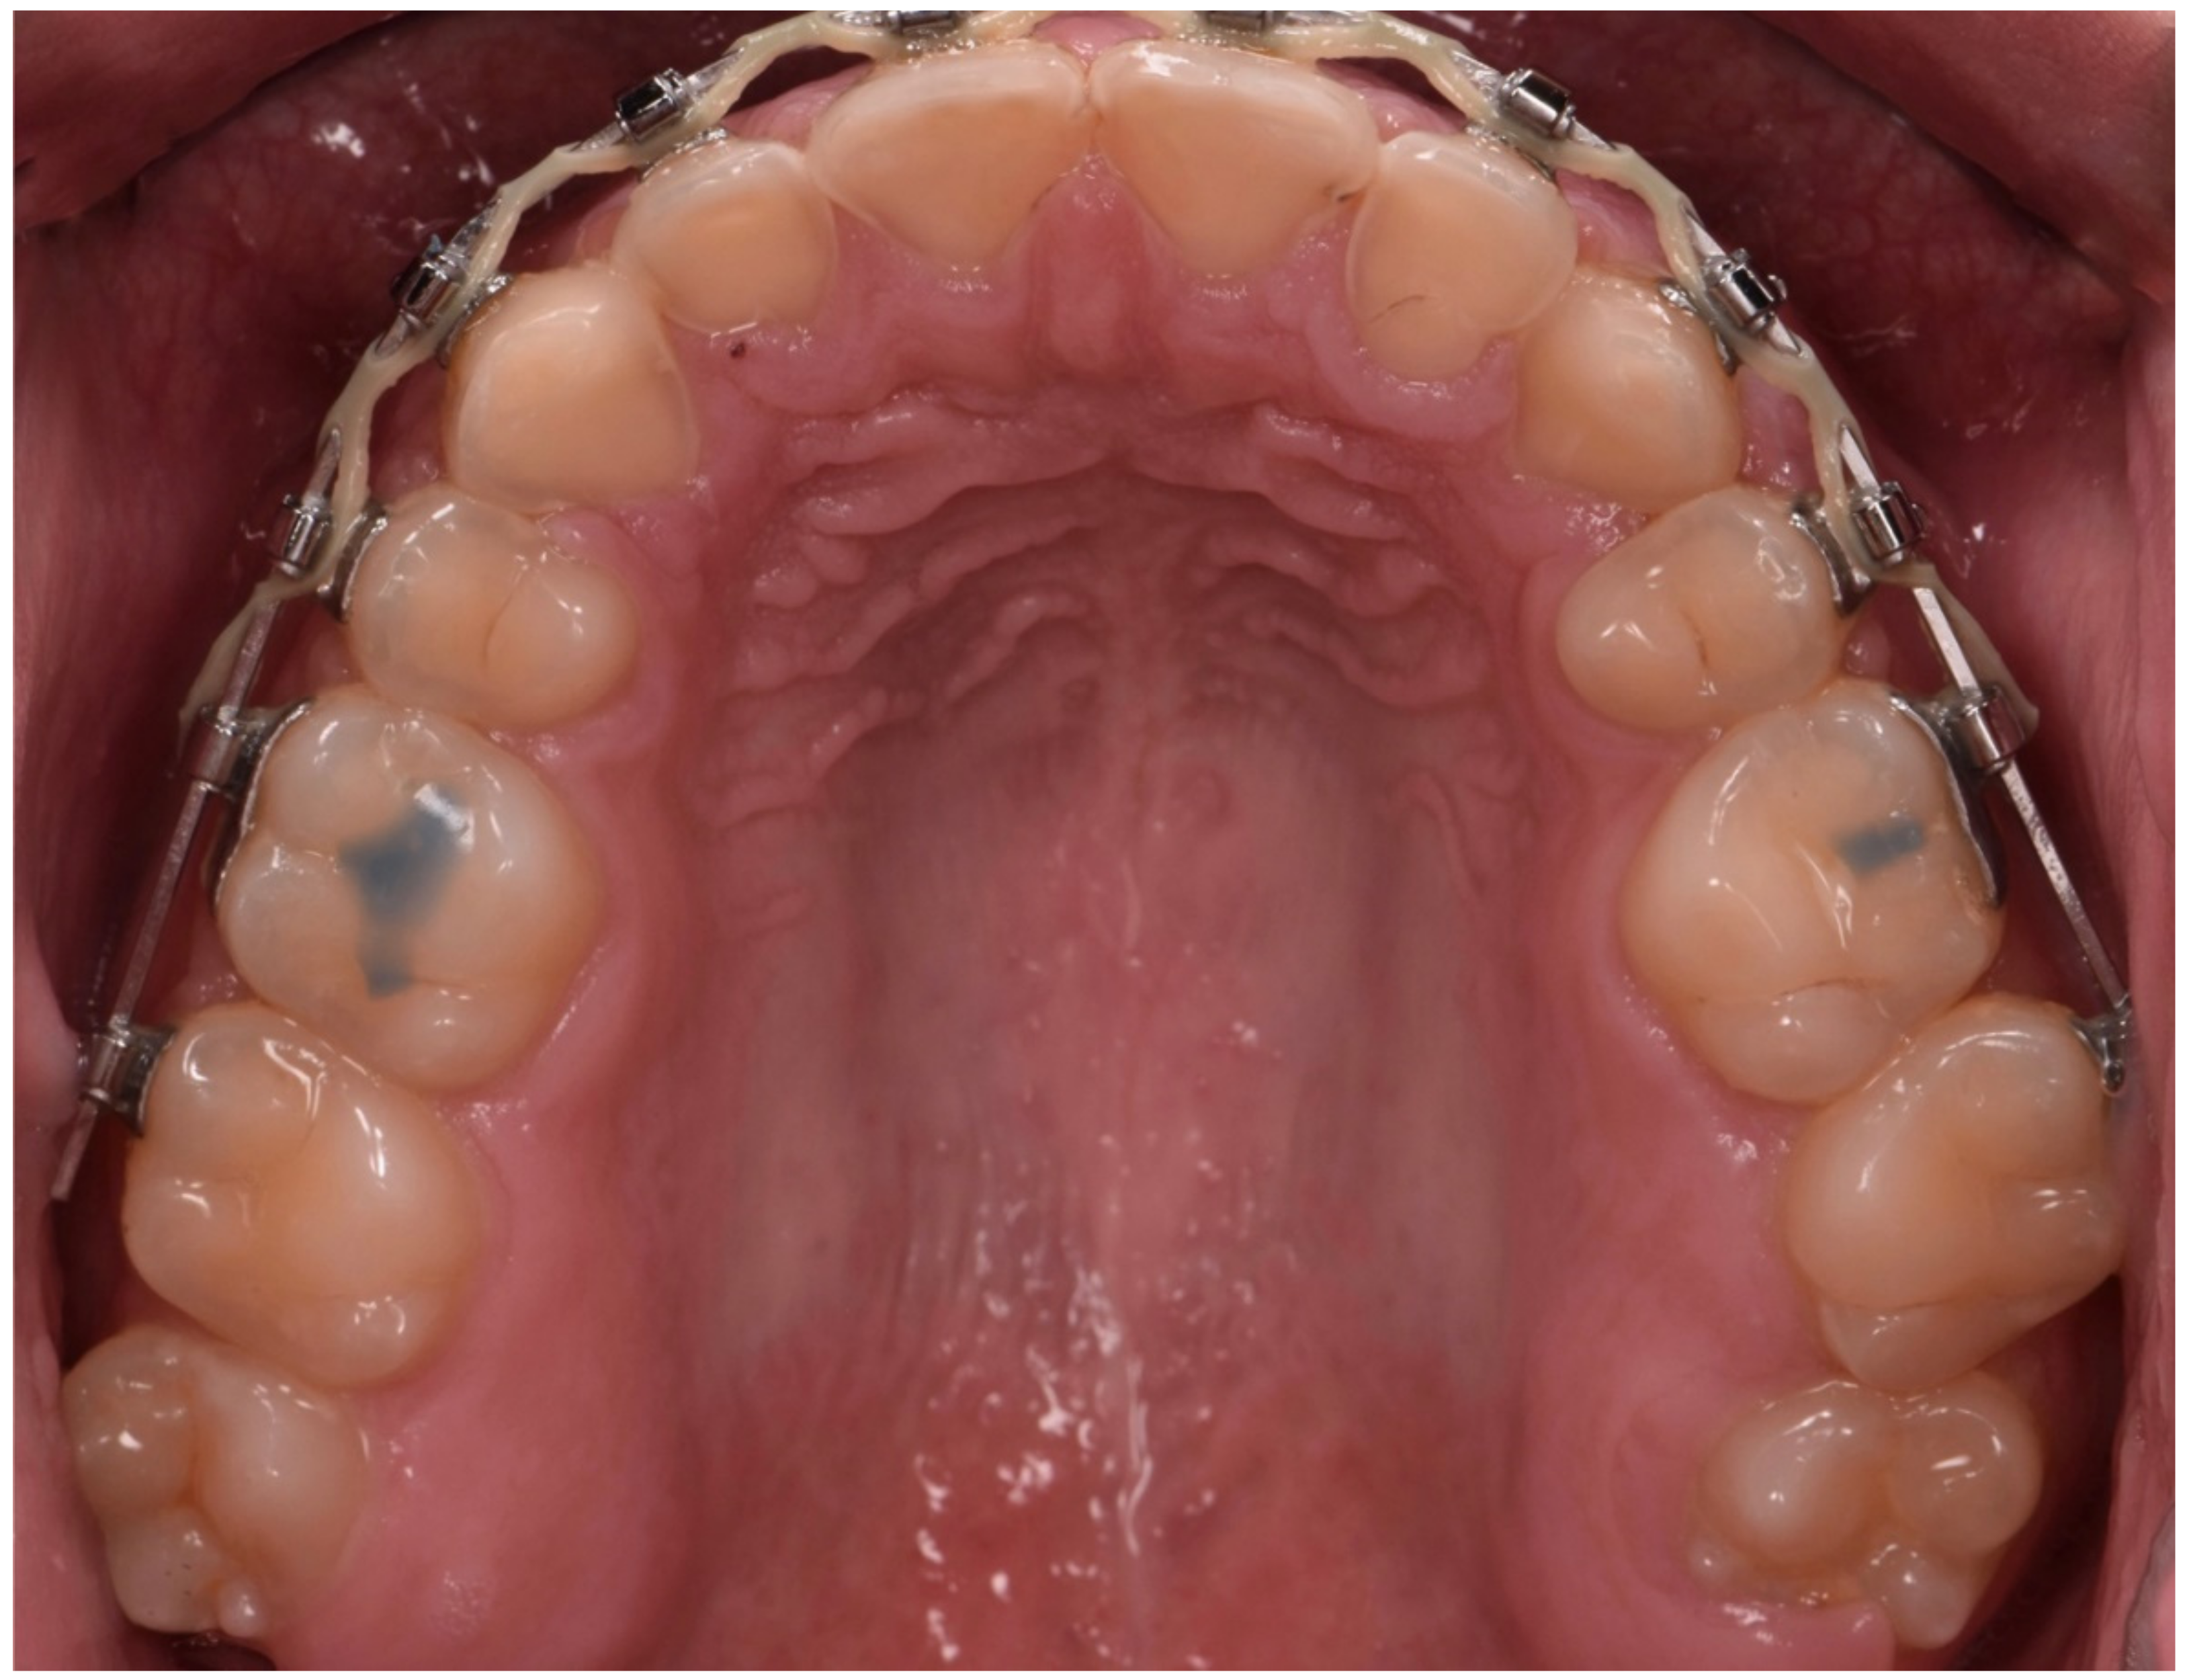

2. Clinical Report

2.1. Planning Phase

2.2. Restorative Phase